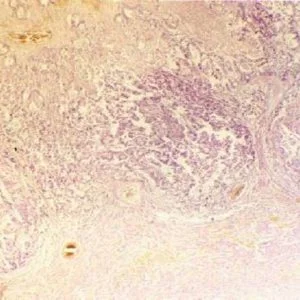

انتشر الحديث في الآونة الأخيرة عن أمراض السرطان وتشخيصه وخطره وانتشاره، وهو أمر طبيعي لما تمثله هذه الأمراض من خطورة، بحيث تقضي على حياة الملايين من البشر سنويا.

لاشك أن التشخيص المبكر للمرض يمنح فرصة أكبر لمكافحة المرض، وأحيانا الشفاء منه تماما، بيد أن المشكلة تكمن في عدم وجود أعراض واضحة ومحددة للمرض في بداياته، لكن هناك علامات معينة تساعد في تشخيص المرض قبل 2-5 سنوات من تطوره.